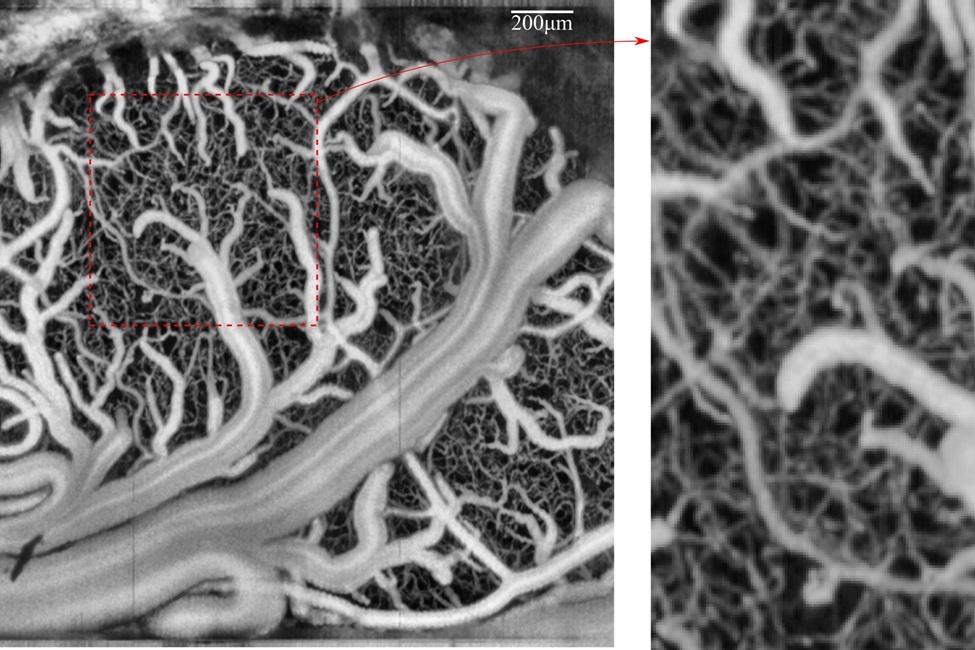

Network of vessels in the brain imaged by the researchers.

The imaging systems developed and used by the researchers.